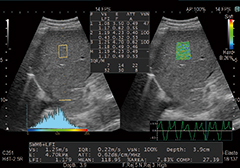

・Shear Wave Measurement(SWM)

プッシュパルスで生体組織を振動させることによって,せん断弾性波(shear wave)が発生します。このせん断弾性波の伝搬速度(Vs)を計測することで,組織の硬さを定量的に評価できます。

・Combi-Elasto

非侵襲的に肝組織の硬さを評価するRTEとSWMが融合。肝線維化および炎症を経時的により精度高く評価できます。さらに肝脂肪化の程度を推定する指標(ATT)も同時に測定でき,肝疾患の総合的な鑑別をサポートします。